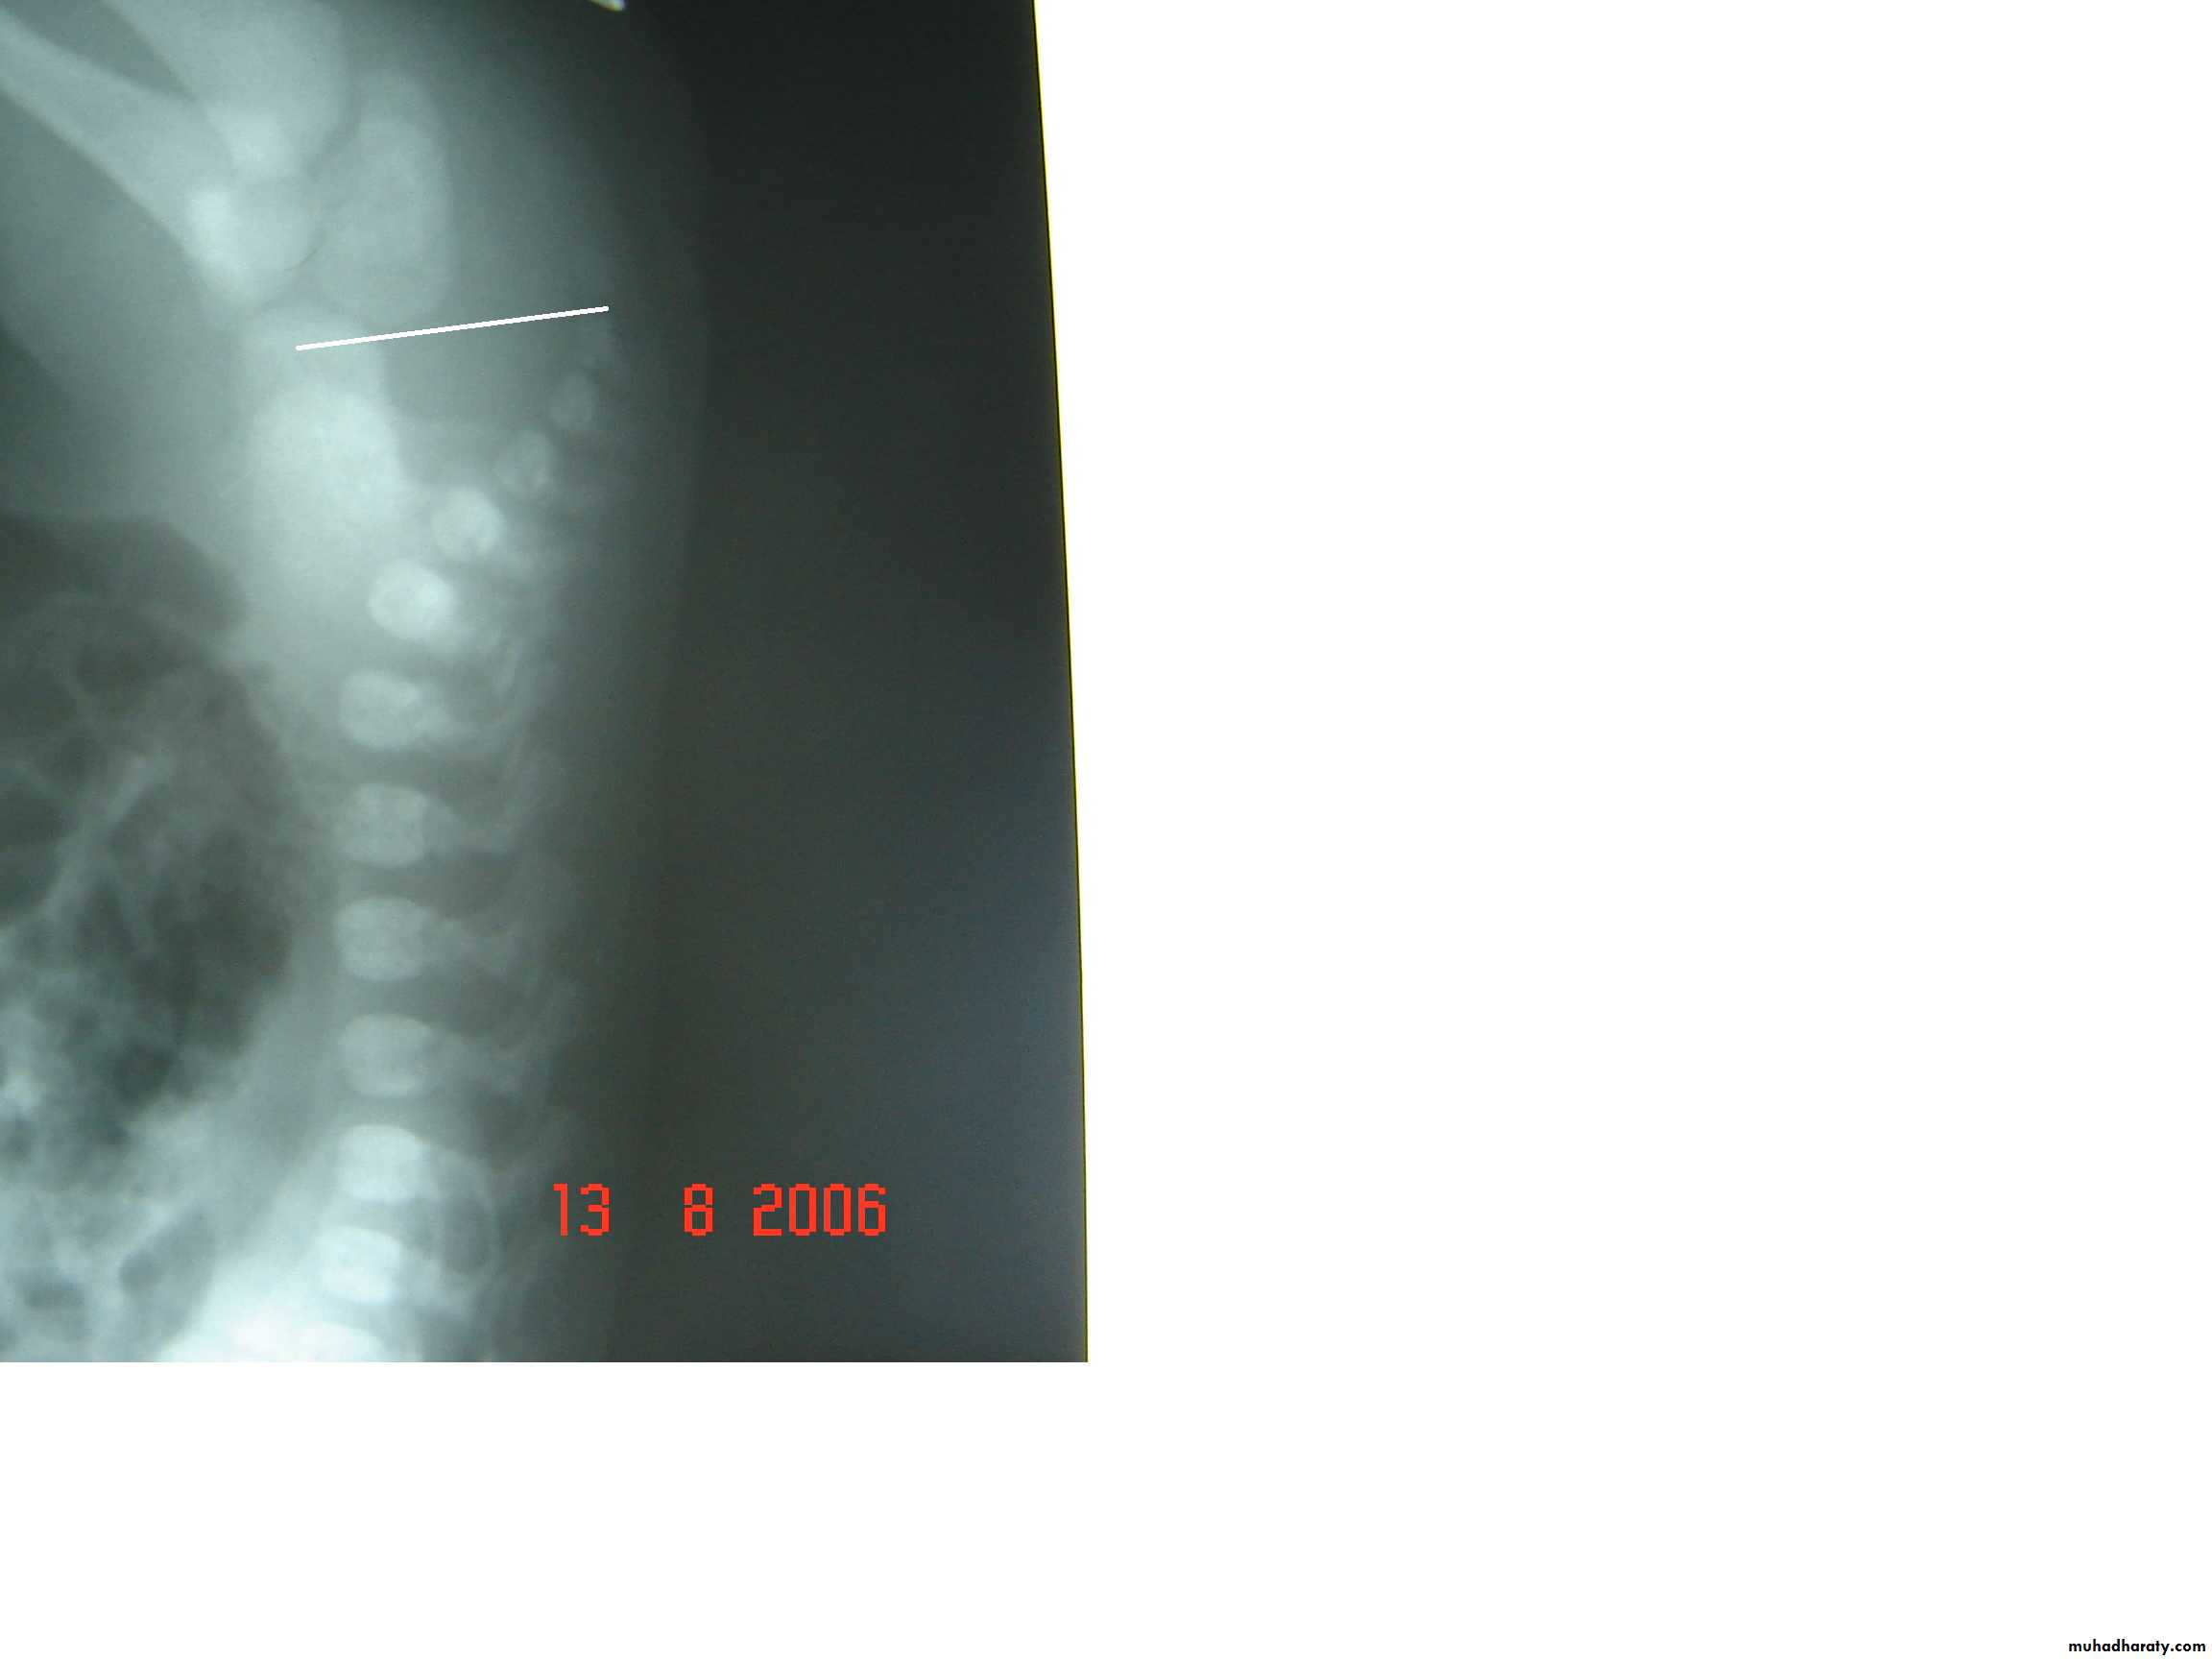

2-Lateral invertogram ( pubococcegeal line) 18-24hr.after birth.

-gas shadow above this line suggest high type.

- gas shadow below suggest low type.

3-lateral decubitus X-ray.